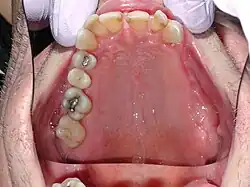

Der Ductus parotideus verläuft beim Menschen über den Musculus masseter und ist an dessen Vorderrand durch die Haut tastbar.[2] Er zieht dann durch den Musculus buccinator in die Wangenwand und mündet im Mundhöhlenvorhof im Bereich des oberen zweiten Mahlzahns.[3] Gelegentlich wird der Gang von Drüsengewebe begleitet (Glandula parotidea accessoria).[4] Die Mündung liegt auf einer kleinen Erhebung, der Papilla ductus parotidei. Dort hat der Gang, wie die Mundhöhle, zunächst noch ein mehrschichtiges Plattenepithel, welches dann in ein zweireihiges prismatisches Epithel übergeht.[5]